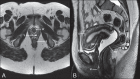

Magnetic resonance imaging is a method with high contrast resolution widely used in the assessment of pelvic gynecological diseases. However, the potential of such method to diagnose vaginal lesions is still underestimated, probably due to the scarce literature approaching the theme, the poor familiarity of radiologists with vaginal diseases, some of them relatively rare, and to the many peculiarities involved in the assessment of the vagina. Thus, the authors illustrate the role of magnetic resonance imaging in the evaluation of vaginal diseases and the main relevant findings to be considered in the clinical decision making process.